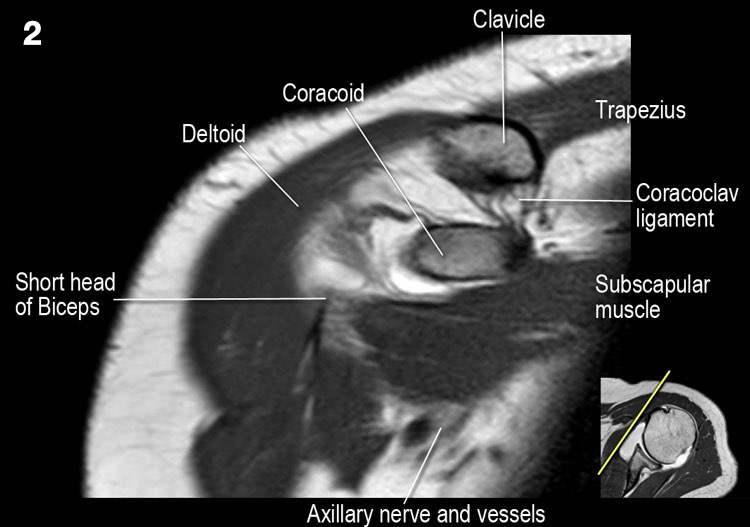

Giải phẫu mặt cắt vành và danh sách kiểm tra

- Lưu ý dây chằng quạ-đòn và đầu ngắn cơ nhị đầu.

- Lưu ý dây chằng quạ-mỏm cùng vai.

- Lưu ý thần kinh và mạch máu trên vai.

- Tìm kiếm hội chứng chèn ép cơ trên gai do gai xương khớp cùng-đòn hoặc dây chằng quạ-mỏm cùng vai dày lên.

- Đánh giá phức hợp sụn viền-gân cơ nhị đầu phần trên và tìm kiếm túi cùng dưới sụn viền hoặc rách SLAP.

- Tìm kiếm tràn dịch quá mức trong túi hoạt dịch dưới mỏm cùng vai và rách gân cơ trên gai.

- Tìm kiếm rách kiểu “rim-rent” của gân cơ trên gai tại chỗ bám của các thớ sợi trước.

- Đánh giá chỗ bám của dây chằng ổ chảo-cánh tay dưới (IGHL) vào xương cánh tay. Đánh giá phức hợp sụn viền-dây chằng phần dưới. Tìm kiếm tổn thương HAGL (bong điểm bám dây chằng ổ chảo-cánh tay tại xương cánh tay).

- Tìm kiếm rách gân cơ dưới gai.

- Lưu ý tổn thương Hill-Sachs nhỏ.